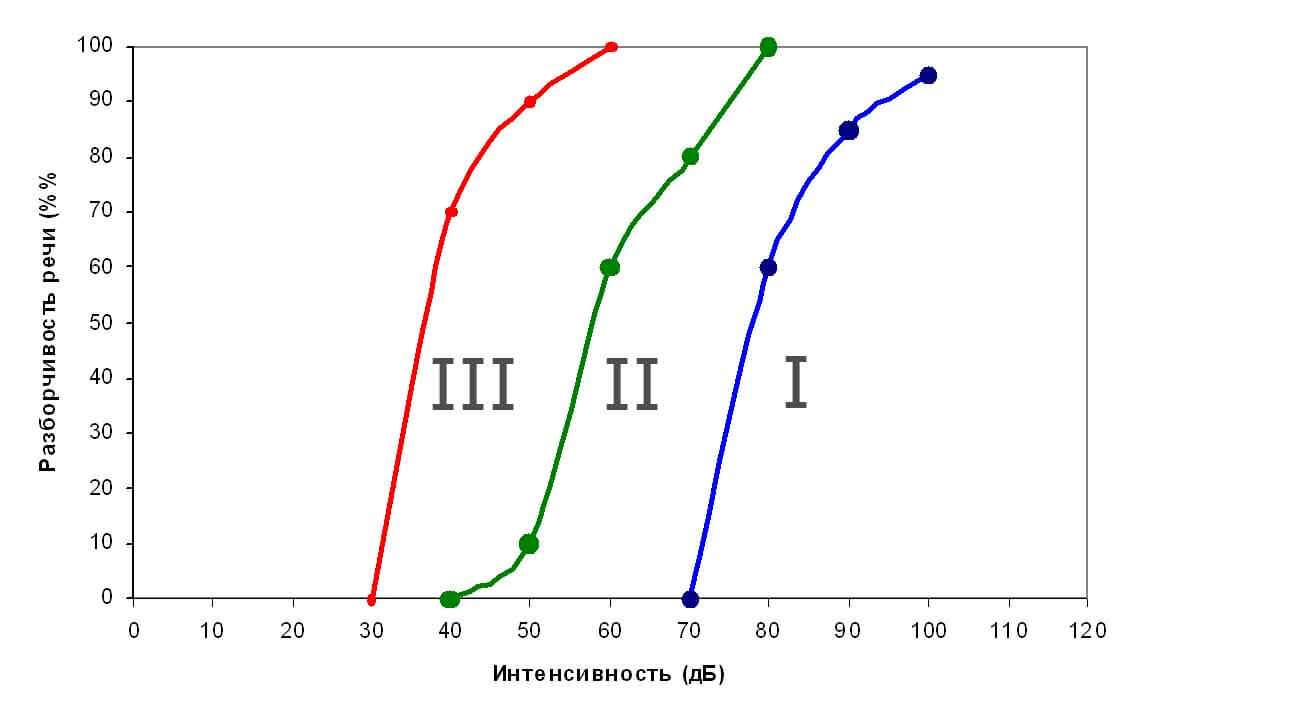

В послеоперационном периоде ни у одного пациента нами не было отмечено отрицательной динамики по слуху в сравнении с дооперационным уровнем. В первые 7 -14 дней у пациентов регистрировалась тимпанограмма тип С, в последующем тип А. Подключение аудиопроцессора мы выполняли через 3 недели после операции и проводили проверку слуха в свободном звуковом поле (речевую аудиометрию). Вторая настройка проводилась через 10 дней после первого подключения. Третья окончательная регулировка аудиопроцессора была проведена нами через 3 недели после второй настройки. Всем пациентам после каждой настройки проводилась речевая аудиометрия в свободном звуковом поле. Результаты речевой аудиометрии в свободном звуковом поле представлены на рисунке 19.

На рисунке синим (I) обозначена разборчивость речи до операции в слуховых аппаратах, зеленым (II) - разборчивость речи при первом подключении, красным (III) - разборчивость речи после третьей настройки. Разборчивость речи у пациентов уже в первые 3 суток после подключения составляла 70% и более, а через 2 недели разборчивость речи достигала 80-90%.